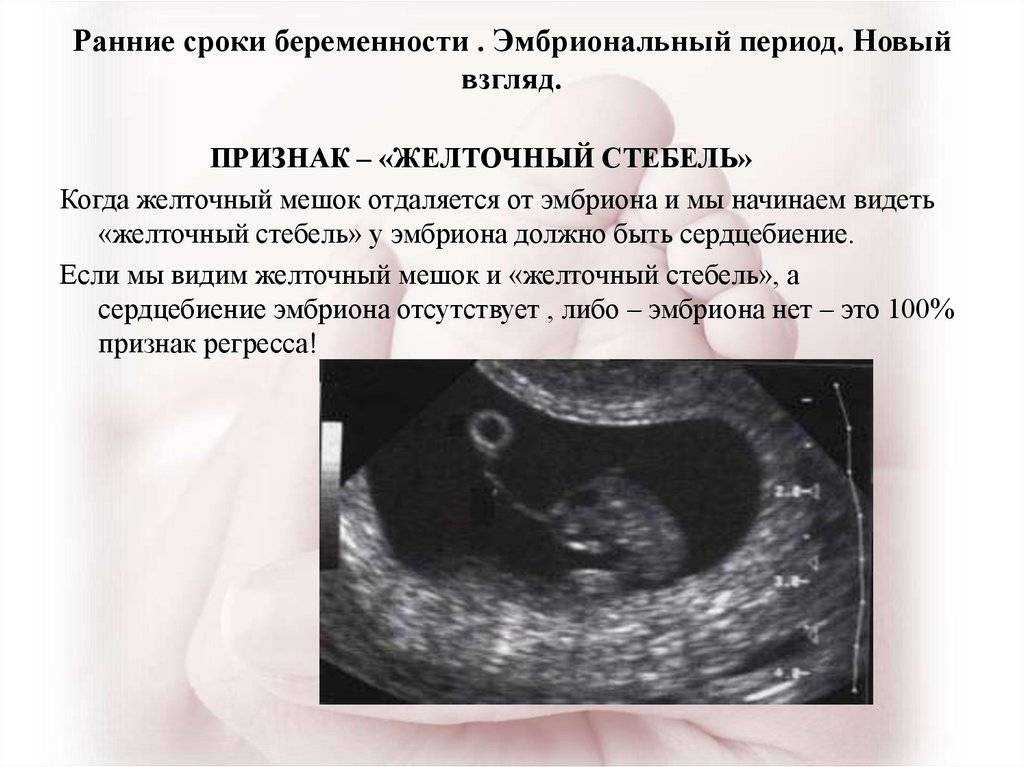

Почему не визуализируется эмбрион?

Иногда в ходе УЗИ на сроке 5–6 недель беременности отмечается отсутствие визуализации эмбриона. У данного явления существует множество причин. Сонологу может быть не виден зародыш из-за наличия объективных (патологических и физиологических) и субъективных факторов. Не всегда требуется принятие срочных лечебных мер.

На экране монитора пустое плодное яйцо визуализируется как черное пятно неправильной формы, как правило меньше по размерам, чем должно быть по сроку беременности. Иногда специалист видит нормальное плодное яйцо округлой формы, но желточный мешок в нем отсутствует. На первых неделях беременности ультразвуковое обследование обладает низкой информативностью, поэтому рекомендуется проходить первое УЗИ на 10–12 неделе – в это время плод уже четко виден.